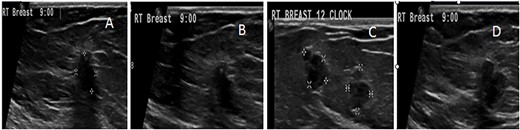

Ultrasonography (US) showed multiple hypoechoic solid lesions scattered in the right upper outer quadrant. The two most suspicious lesions measured 7 × 5 and 5 × 4 mm, and the rest were <1 cm. One of these lesions showed a microlobulated border, whereas the other had an indistinct border. Based on the Breast Imaging Reporting and Data System (BI-RADS), they were classified as BI-RADS IV A (Fig. 1). Mammography showed innumerable dense lesions in the upper outer quadrant and retro-areolar area. Some had indistinct borders, whereas others were serrated. Linear and cluster microcalcification foci also appeared. These findings led to a classification upgrade to BI-RADS IV C (Figs 2 and 3). The first core needle biopsy (CNB) indicated papilloma with ADH from one lesion and degenerated cyst content with histocytes from the other lesion without any signs of infiltrated malignancy. The patient was given the option of excisional biopsy; however, she opted for alternative medicine.

Ultrasound (US) scan of the right breast revealed innumerable hypoechoic breast lesions. (A) Some of them appear round with well-defined regular borders. (B) Others show microlobulated borders with additional dilated duct beside. (C) Others show indistinct borders.